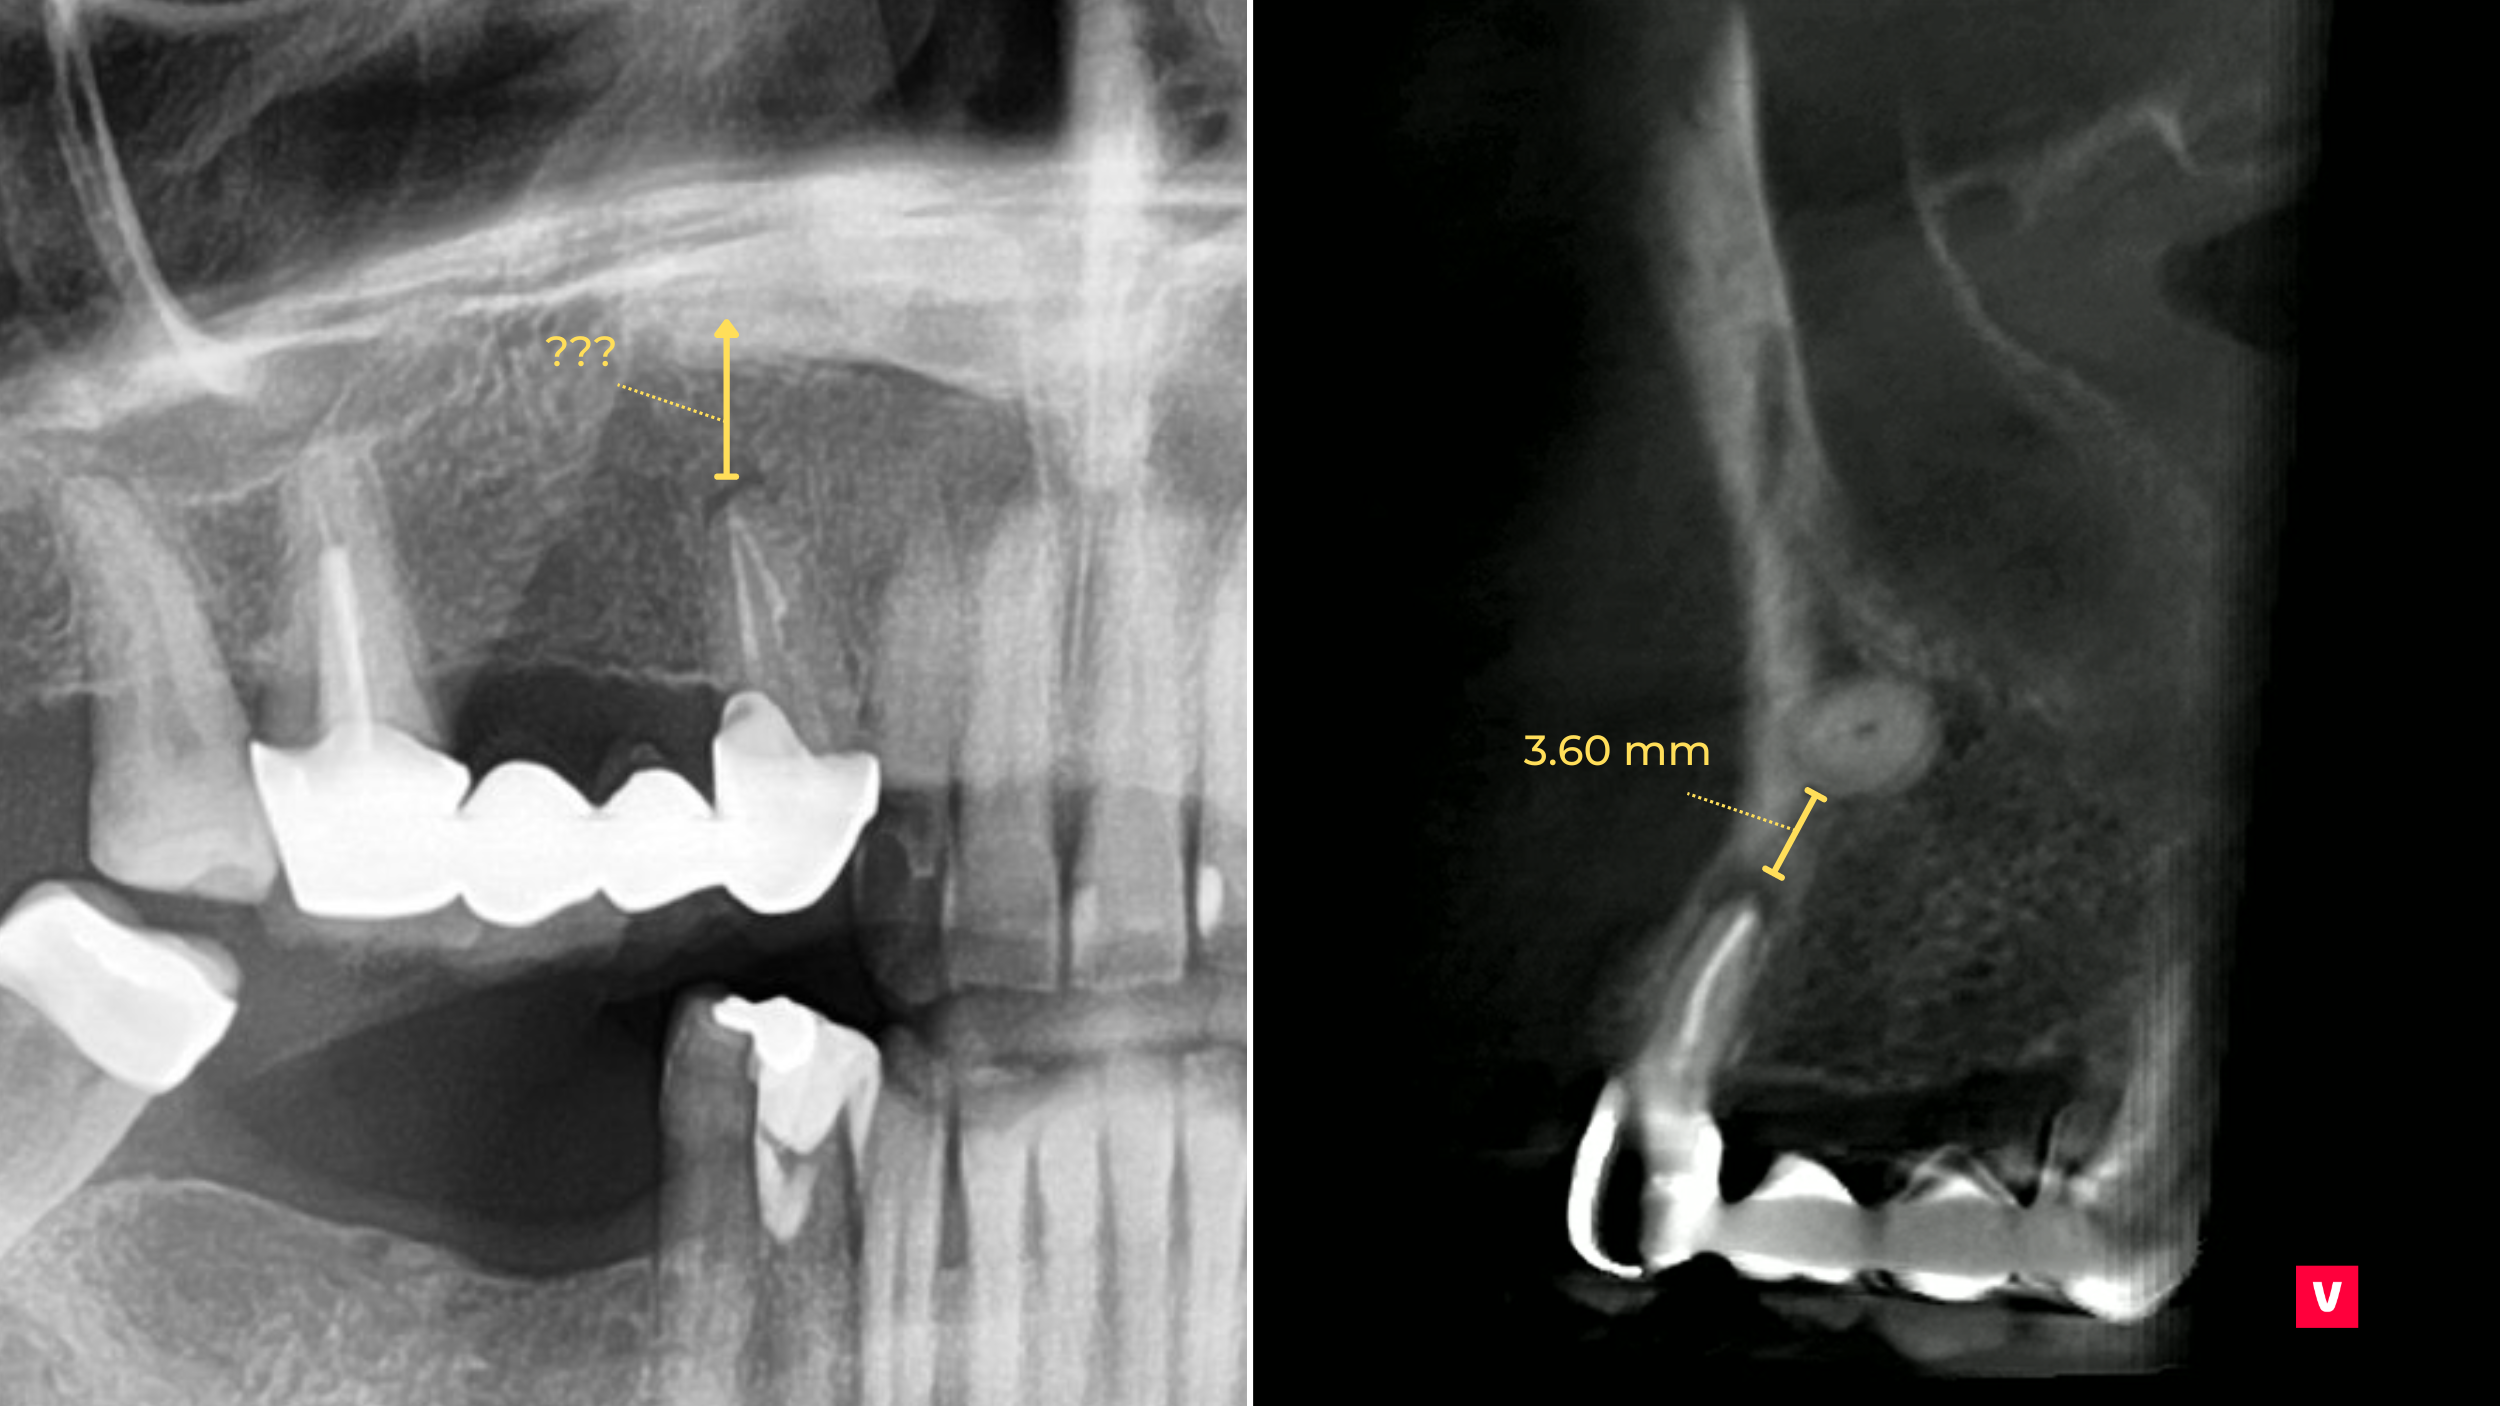

În studiul de caz pe care îl dezbatem în acest articol vom vedea cum depistarea unei astfel de complicații s-a putut observa doar în cazul unei examinări detaliate, ceea ce nu s-a putut observa după o scanare OPG (ortopantomografie), din cauza asimetriei din regiunea maxilarului. Doar cu ajutorul unei imagini CBCT 3D s-a văzut că pacientul are un dinte ascuns în regiunea maxilarului superior drept care ar fi putut provoca complicații grave dacă nu ar fi fost descoperit la timp.

Din păcate, imaginile OPG nu oferă întotdeauna informațiile necesare pentru măsurarea corectă, iar distanța poate fi destul de distorsionată. Însă, distorsiunea nu este o îngrijorare pentru utilizatorii Ez3D-i, deoarece software-ul este echipat cu mai multe opțiuni de măsurare diferite, cum ar fi măsurarea lungimii, a lungimii multiple, a unghiurilor sau a razei unui cerc. Toate aceste funcții pot fi realizate cu ajutorul informațiilor adunate în timpul scanării 3D, astfel încât precizia lor este mult mai mare.

După cum se poate observa în acest studiu de caz prezentat, dintele ascuns în maxilar este mult mai aproape decât pare la o scanare OPG obișnuită. Acest lucru ar putea cauza unele probleme în timpul procedurilor stomatologice. Medicul stomatolog a identificat anomalia la timp, prevenind astfel complicațiile.